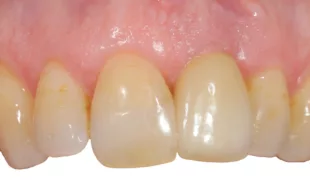

Für den Knochenaufbau wurde Geistlich Bio-Oss Collagen in den Defekt appliziert und nach der Augmentation die Eingriffsstelle mit einem Kollagenvlies abgedeckt. Weitere 6 Monate nach dem Eingriff wurde die endgültige Kronenrestauration eingesetzt. Bei der weiteren Nachuntersuchung nach nunmehr 25 Jahren zeigte die Röntgenaufnahme ein stabiles Implantatlager und das klinische Bild bei der Nachkontrolle einen ästhetischen Zahnstatus.